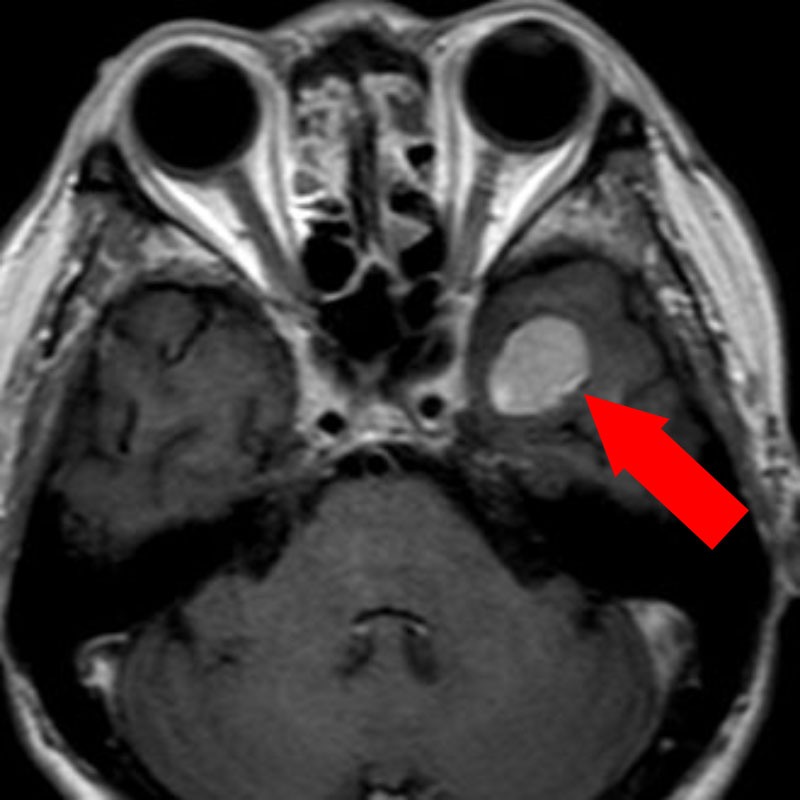

No.’24_20 手術前1

No.’24_20 手術前2

No.’24_20 摘出 前

No.’24_20  摘出 中

No.’24_20 摘出 後